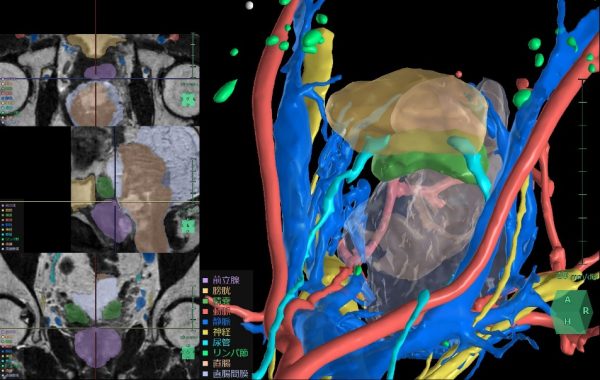

膀胱周辺臓器解析

術前のCT画像やMR画像から3D構築を行うことで、骨盤腔内の膀胱周辺臓器や神経、血管の位置関係を把握し、患者ごとに異なる血管走行などの解剖学的特徴を把握し、手術シミュレーションを行うことができる。

すでに解析機能を提供している直腸と同様に、 骨盤内に位置する膀胱や前立腺の手術においても周囲の血管や尿管、臓器の位置関係の把握は非常に重要である。このニーズに対応して、骨盤内の泌尿器科領域に対応したアプリケーション「膀胱周辺臓器解析」を新たにリリースする。この機能により膀胱周囲の臓器や神経、血管の位置把握を支援することで、前立腺癌や膀胱癌手術時のリンパ節郭清等において手術リスクの低減と治療成績の向上への貢献が期待される。